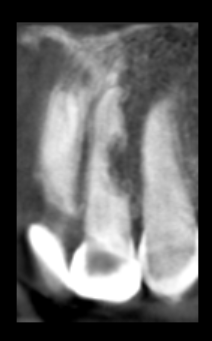

Reabsorciones radiculares, cuáles son sus causas

Las reabsorciones radiculares son difíciles de diagnosticar su etiología y menos de explicar al paciente un problema que no siente. La...